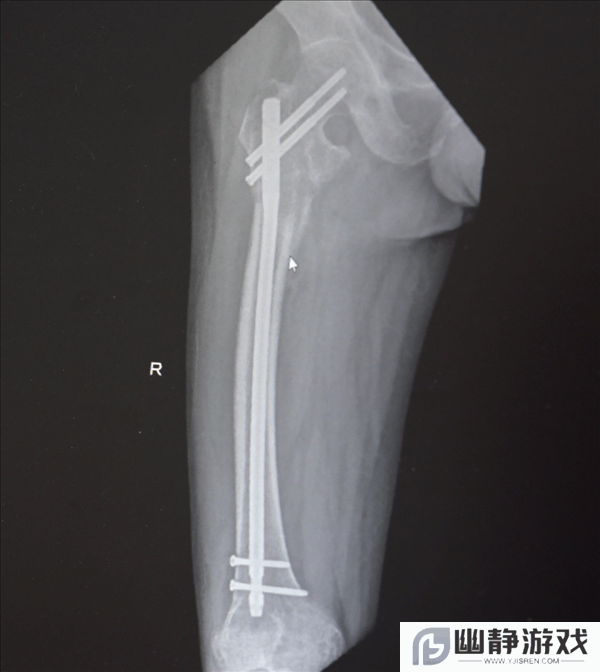

创伤性失血性休克、多发性肋骨骨折、肺部损伤、右侧肩胛骨粉碎骨折、右侧肱骨髁上开放粉碎性骨折、右股骨粗隆及股骨干粉碎性骨折、骨盆粉碎性骨折、腰椎横突多发骨折、腰骶柱神经损伤、臂丛神经损伤、胸腔积液、腹腔积液等。

经医生检查,张先生全身共有六处较大骨折部位,多为严重粉碎性骨折,全身骨折碎块达30多块!